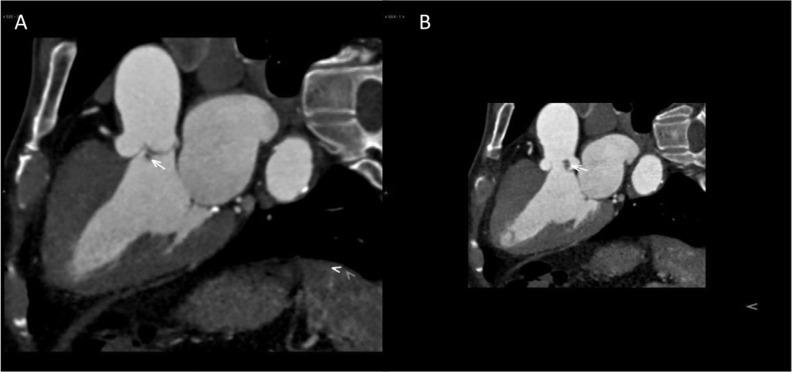

Papillary Fibroelastomas are rare, primary cardiac tumors. They are typically diagnosed as an incidental finding but can also present as thrombo-embolic events. We present the case of 78-years- old man who presented to emergency room with a cerebrovascular event (CVE). Transesophageal echocardiography (TEE) revealed e presence of a mass on the aortic valve. Intra-operatively, two masses where found: one was highly mobile attached to left ventricular (LV) side of the left coronary cusp, another small size mass attached to the non-coronary cusp, and there was suspicion of a mass attached to the mitral valve. The two masses were surgically excised using a right mini-thoracotomy, and histopathological examination confirmed the diagnosis."

乳头状纤维弹性瘤是罕见的原发性心脏肿瘤。它们通常是在偶然检查中被诊断出来,但也可能表现为血栓栓塞事件。我们报告一例78岁男性患者,因脑血管事件(CVE)就诊于急诊室。经食管超声心动图(TEE)显示主动脉瓣上有一个肿块。术中发现两个肿块:一个高度活动,附着于左冠状动脉瓣叶的左心室(LV)侧,另一个小肿块附着于无冠状动脉瓣叶,并且怀疑有一个肿块附着于二尖瓣。通过右胸小切口手术切除了这两个肿块,组织病理学检查确诊。